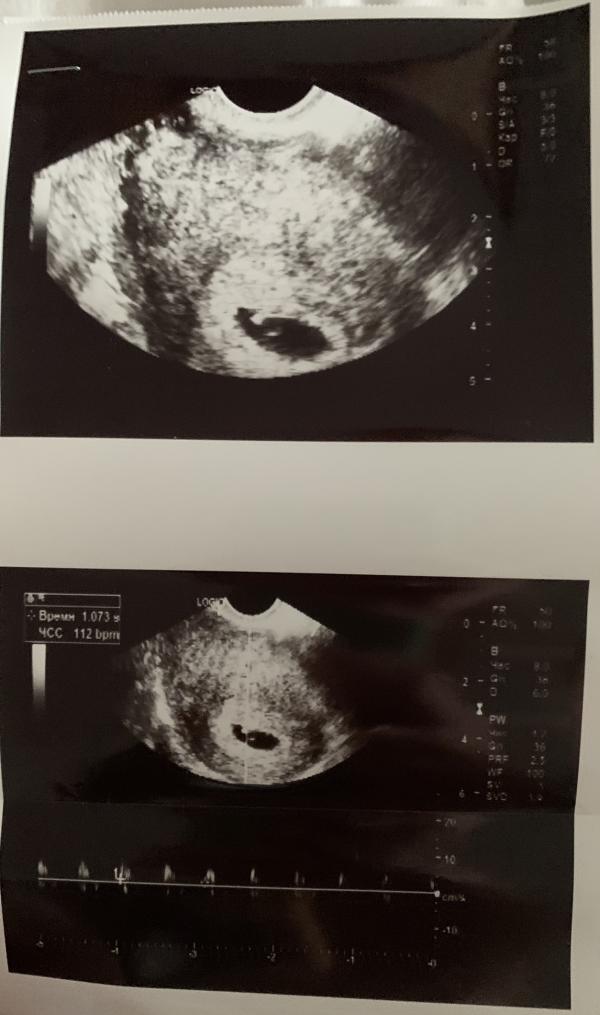

Все соответствует сроку . Расхождение один денёчек . По узи 6 н 2 дня , по кд 6 н 3 дня

Сердечко стучит ❤️❤️❤️

Да . Сегодня 6 н и 4 дня

Месячные были 7.08.2022